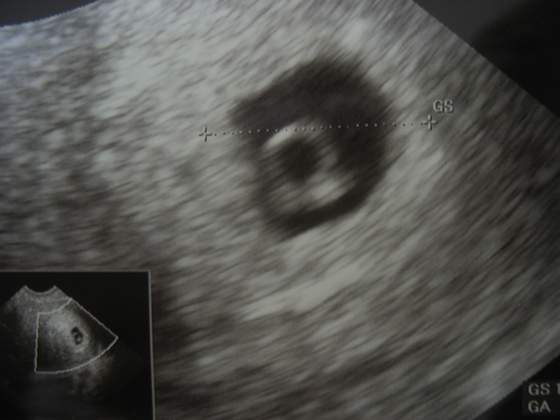

Według poczęcia to 28 dni po ( 4 tygodnie)..a USG pokazuje 5 tydzień i 3 dni:-)Czyli rośnie szybko!Jeszcze tak dobrze nie widać kształtu..ale jest!

Nie nie..dokładnie taka sama, bo USg było robione w czwartek:-)5tygodni i 5 dni dzisiaj:-)Ale znam dzień owulki-i wychodzi,że ciąża szybko się rozwija (bo według tego niecałe 5 tygodni:-)

U mnie suwaczek o dziwo dobrze pokazuje, bo od miesiączki to byłby już prawie 8 tydzień (mam długie cykle 37 dniowe) i ginka też mi liczyła ten 5 tydzień właśnie od poczęcia:-)i według wykresu wszystko się zgadza:-)Oby fasoleczka dobrze rosła!!!!

U mnie suwaczek pokazuje wszystko dobrze, lekarz mi mowił że fasolka szybko sie rozwija.